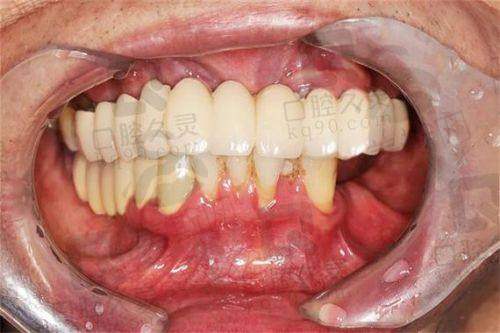

植牙技術:全口即刻負重,香港價格(HKD):12萬 - 30萬,適合人群:想快啲有牙用、唔想長期缺牙嘅人,特點:當日種牙當日戴臨時牙,3日內可正常飲食

植牙技術:All - on - 4全口,香港價格(HKD):15萬 - 35萬,適合人群:牙槽骨條件中等、預算中高嘅人,特點:上下各4顆種植體,穩定性夠,恢復快

植牙技術:All - on - 6全口,香港價格(HKD):18萬 - 40萬,適合人群:想更穩定、經常食硬嘢嘅人,特點:上下各6顆種植體,承重更好,適合食牛腩、蘋果

植牙技術:穿顴穿翼全口,香港價格(HKD):35萬 - 60萬,適合人群:牙槽骨嚴重吸收、無法植骨嘅長輩,特點:直接打釘入顴骨,唔使植骨,手術難度高